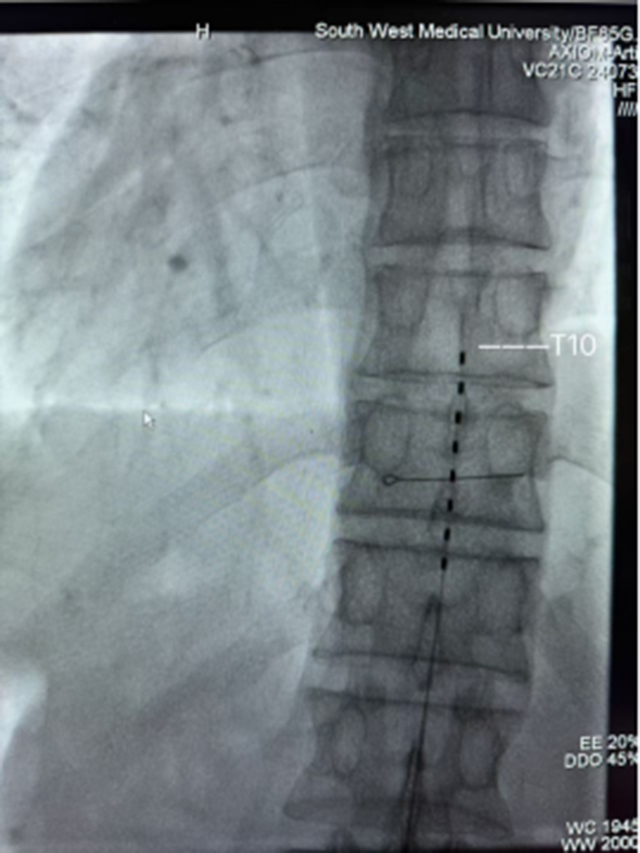

手术室里,气氛紧张而凝重。在张英教授的带领下,徐力和韩聪医生在DSA引导下有条不紊地进行脊髓电刺激系统植入术。随着一次性脊髓神经刺激测试电极缓缓植入,安置位置理想,当进行程控时,古先生的会阴区传来酥麻感,且基本覆盖了疼痛区域,原本紧皱的眉头瞬间舒展开来。